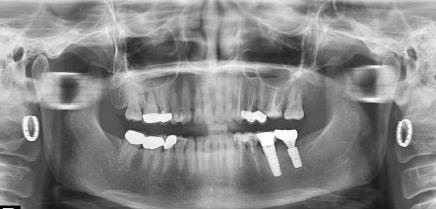

種植牙複診拍片

種植牙複診時需要拍片嗎?

種植牙複診一般都需要拍片的,主要是因為(wei) 種植牙的人工牙根是植入到牙槽骨裏麵的,肉眼無法的查看人工牙根在裏麵的情況,隻能通過牙片把人工牙根和牙槽骨的情況展現出來,查看種植體(ti) 是否有鬆動或者炎症等情況。